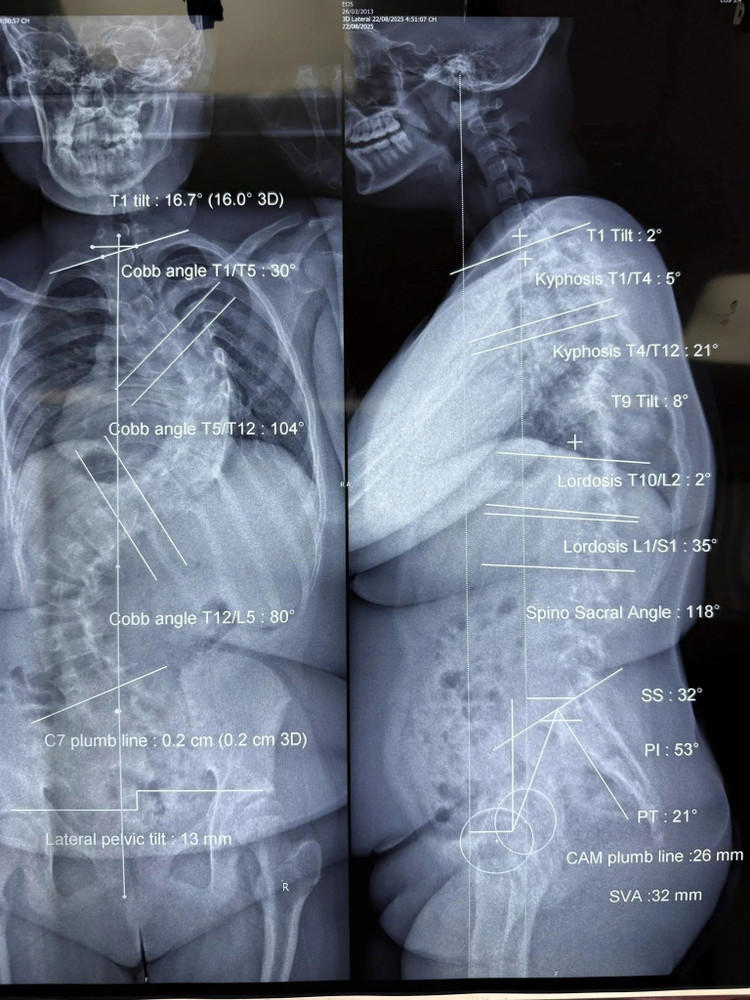

Nhiều bệnh viện trước đó đã từ chối phẫu thuật vì rủi ro gây mê vượt ngưỡng an toàn. Chỉ trong 7 tháng chờ đợi phẫu thuật, độ vẹo cột sống của L tăng nhanh từ 78 độ lên 104 độ, kéo theo đường cong thứ hai 80 độ ở vùng thắt lưng. Mẹ bé từng run rẩy không dám đặt bút ký giấy cam kết phẫu thuật.

Hình ảnh cột sống cong vẹo trên phim chụp của các bệnh nhi - Ảnh BVCC